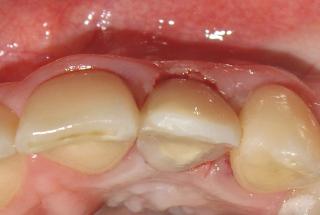

Clinical cases

MPI closely monitors clinical cases in the market to ensure their correct functioning and successful outcome.